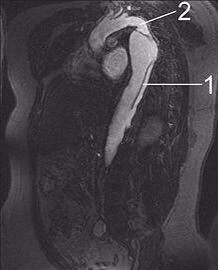

3、磁共振血管成像(MRA)也是诊断好方法,但测量血管内径上不够精确。